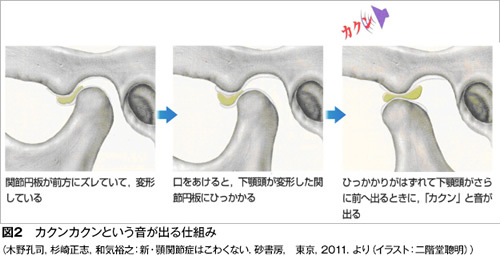

顎関節症の病気の状態(病態)は現在4つに分類されています。最も多いのは関節内にある関節円板(図1)というクッションが前方にずれることで起きる「カクンカクン」という音が出る状態(図2)、あるいはずれがもっと大きくなることで大きな口が開けられなくなる状態です(図3)。